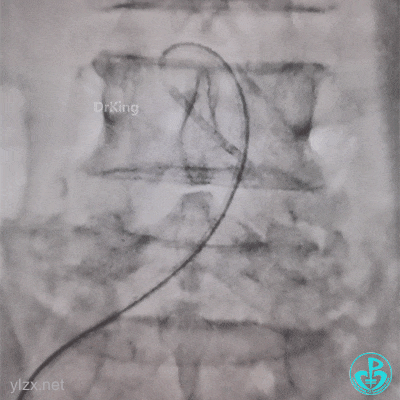

J-W软头端无法通过管子。

换硬头端(铤而走险、不常规推荐)。

管子头还是打不开,调整一下。

打折处通了,换软头端(直头端不敢出GC)。

管子头段直啦。

拉出来了。